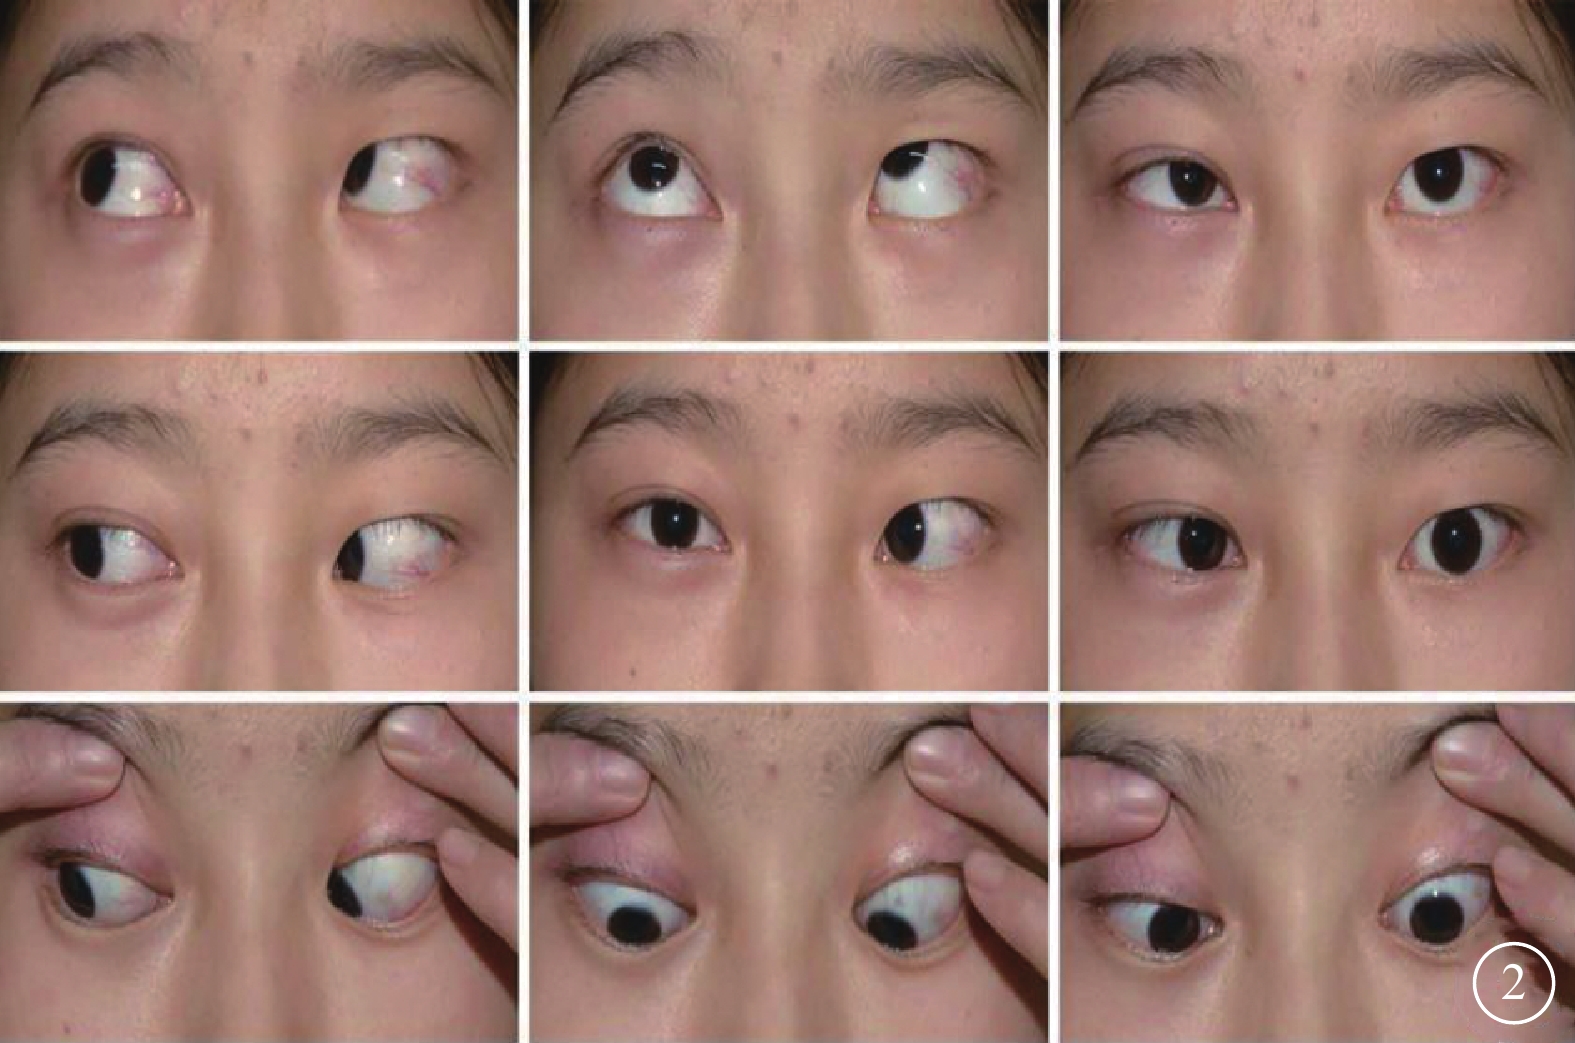

患者女,18歲。2010年9月因頭枕部外傷致意識喪失入院。醒后發現左眼內斜、眼球運動障礙、視力下降伴口角右偏。眼眶CT檢查未見異常;頭顱MRI檢查顯示小腦蚓部出血致雙側小腦半球、第四腦室及背側腦橋受壓變形(圖1)。傷后10 d行顱內血腫清除手術。手術后上述癥狀無改善且逐漸出現左眼瞼閉合不全、視力逐漸下降。為求進一步診治于2015年12月到我科就診。否認既往眼病及全身病史。眼部檢查:右眼視力1.0;左眼視力0.1,不能矯正。雙眼瞳孔等大,對光反射靈敏;左眼相對性瞳孔傳入性障礙(+)。雙眼視盤邊界清楚,顏色淡,以左眼為著;黃斑中心凹反光清晰。雙眼眼壓正常。視野檢查,右眼生理盲點擴大,鼻下象限視野部分缺損,視敏度下降;左眼顳側及鼻上象限視野不規則缺損。光相干斷層掃描檢查,雙眼視盤周圍視網膜神經纖維層變薄。眼位檢查,右眼注視時左眼內斜約30°;左眼注視不良。眼球運動檢查,右眼外展正常伴輕度水平眼球震顫,內收受限,鼻側角膜緣僅到達上、下淚小點連線;左眼外展受限,顳側角膜緣剛過中線,內收正常(圖2),單眼和雙眼運動相同;輻輳反射正常。神經系統檢查,左側額紋消失,瞼裂閉合不全,鼻唇溝變淺,舌前2/3味覺減退;口角向右偏斜,鼓腮時左側漏氣。診斷:(1)麻痹性內斜視;(2)非典型性八個半綜合征;(3)外傷性視交叉病變;(4)雙眼視神經萎縮。行左眼上、下直肌1/2轉位聯合內直肌后退手術。手術后眼位正,隨訪半年眼位穩定。

眼位及眼球運動檢查圖。左眼內斜,外轉受限;右眼內轉輕度受限

眼位及眼球運動檢查圖。左眼內斜,外轉受限;右眼內轉輕度受限

患者女,18歲。2010年9月因頭枕部外傷致意識喪失入院。醒后發現左眼內斜、眼球運動障礙、視力下降伴口角右偏。眼眶CT檢查未見異常;頭顱MRI檢查顯示小腦蚓部出血致雙側小腦半球、第四腦室及背側腦橋受壓變形(圖1)。傷后10 d行顱內血腫清除手術。手術后上述癥狀無改善且逐漸出現左眼瞼閉合不全、視力逐漸下降。為求進一步診治于2015年12月到我科就診。否認既往眼病及全身病史。眼部檢查:右眼視力1.0;左眼視力0.1,不能矯正。雙眼瞳孔等大,對光反射靈敏;左眼相對性瞳孔傳入性障礙(+)。雙眼視盤邊界清楚,顏色淡,以左眼為著;黃斑中心凹反光清晰。雙眼眼壓正常。視野檢查,右眼生理盲點擴大,鼻下象限視野部分缺損,視敏度下降;左眼顳側及鼻上象限視野不規則缺損。光相干斷層掃描檢查,雙眼視盤周圍視網膜神經纖維層變薄。眼位檢查,右眼注視時左眼內斜約30°;左眼注視不良。眼球運動檢查,右眼外展正常伴輕度水平眼球震顫,內收受限,鼻側角膜緣僅到達上、下淚小點連線;左眼外展受限,顳側角膜緣剛過中線,內收正常(圖2),單眼和雙眼運動相同;輻輳反射正常。神經系統檢查,左側額紋消失,瞼裂閉合不全,鼻唇溝變淺,舌前2/3味覺減退;口角向右偏斜,鼓腮時左側漏氣。診斷:(1)麻痹性內斜視;(2)非典型性八個半綜合征;(3)外傷性視交叉病變;(4)雙眼視神經萎縮。行左眼上、下直肌1/2轉位聯合內直肌后退手術。手術后眼位正,隨訪半年眼位穩定。

眼位及眼球運動檢查圖。左眼內斜,外轉受限;右眼內轉輕度受限

眼位及眼球運動檢查圖。左眼內斜,外轉受限;右眼內轉輕度受限